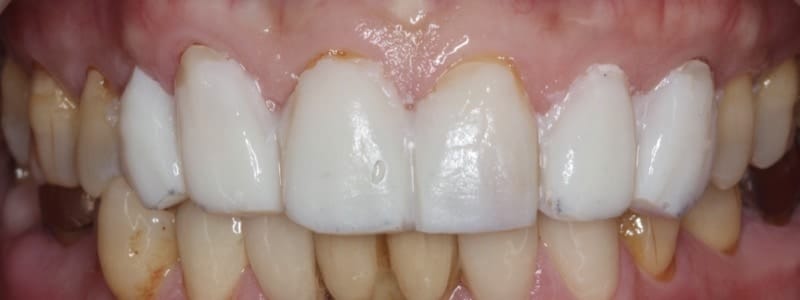

他對右下兩顆用全瓷修復的成果感到非常美觀且滿意,陸續開始計畫接受左下的側門牙和犬齒的全瓷貼片療程,以及評估上顎前牙美觀區全瓷貼片的條件。

圖示:完成全瓷貼片的左下側門牙和犬齒